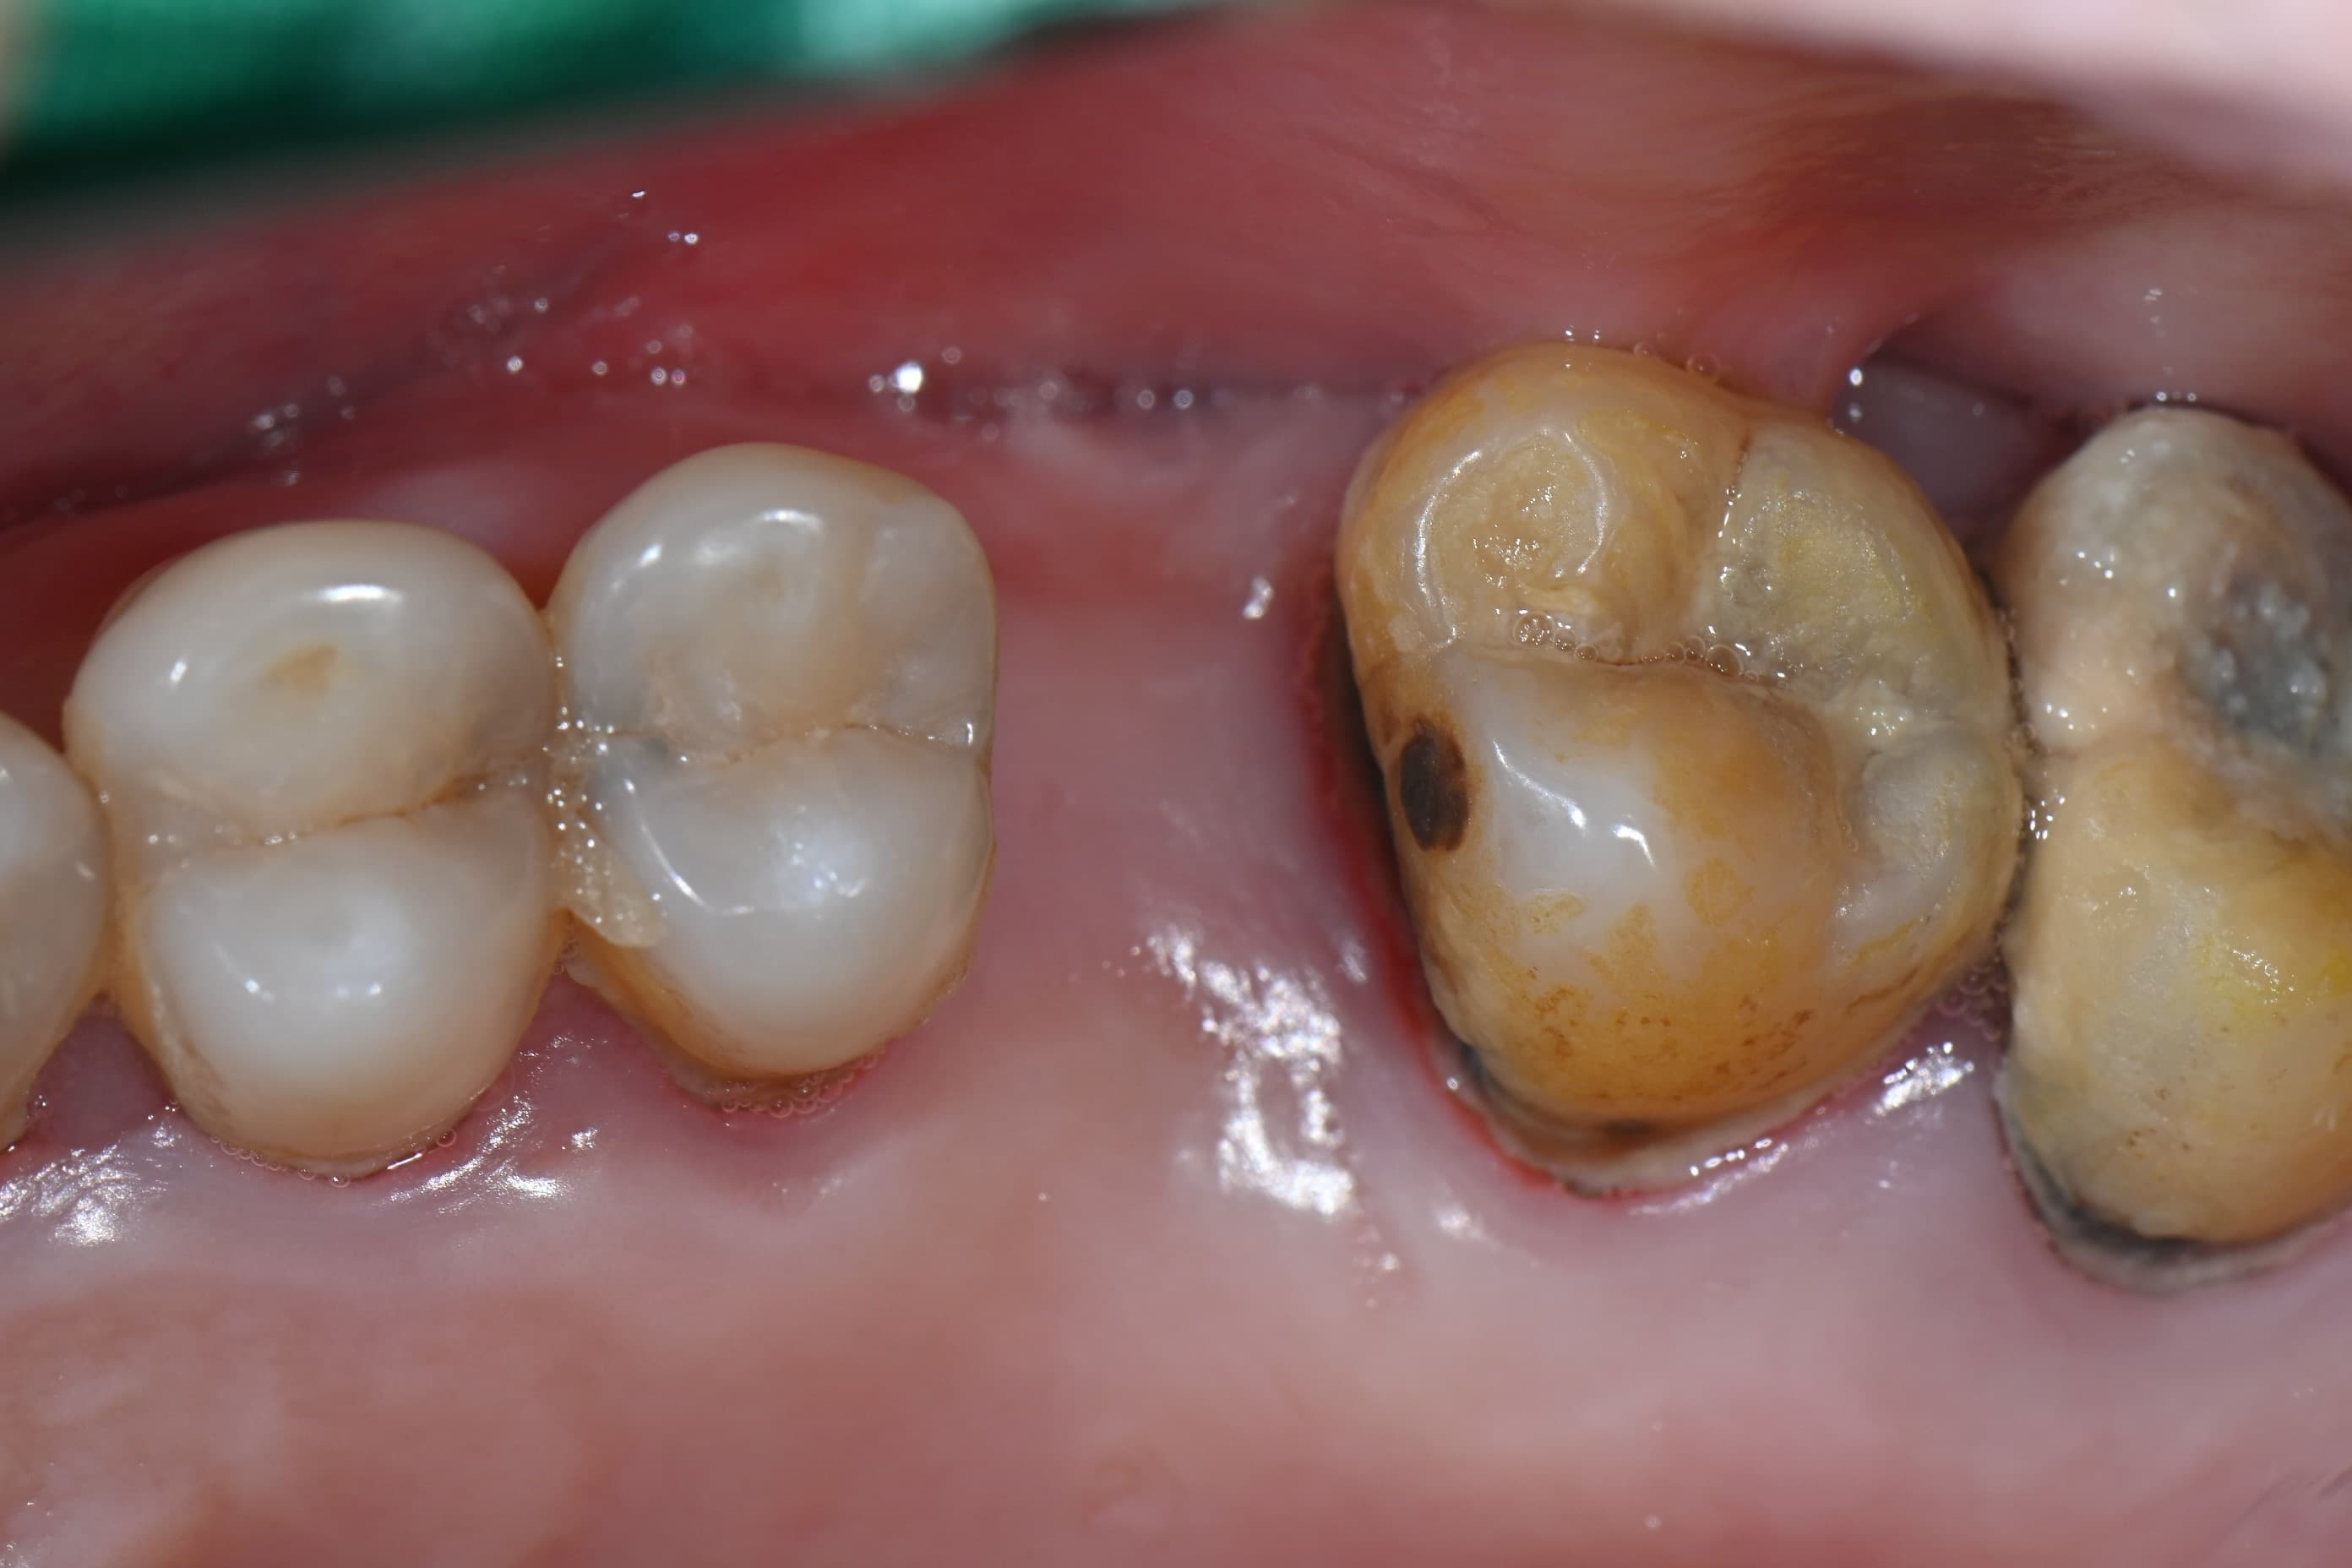

다수 임플란트 · 실제사진 · 지●● · 남성

Before

After

임플란트 · 실제사진 · 이●● · 여성